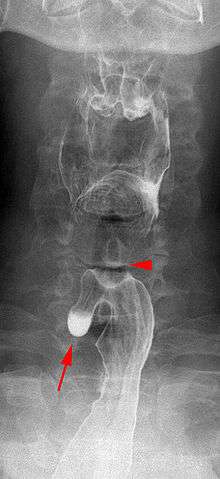

Killian–Jamieson diverticulum. Arrowhead points at the closed upper esophageal sphincter, arrow points at the diverticulum partly filled with contrast medium.

A Killian–Jamieson diverticulum is an outpouching of the esophagus just below the upper esophageal sphincter.[1]

The physicians that first discovered the diverticulum were Gustav Killian and James Jamieson. Diverticula are seldom larger than 1.5 cm, and are less frequent than the similar Zenker's diverticula. As opposed to a Zenker's, which is typically a posterior and inferior outpouching from the esophagus, a Killian–Jamieson diverticulum is typically an anterolateral outpouching at the level of the C5-C6 vertebral bodies, due to a congenital weakness in the cervical esophagus just below the cricopharyngeal muscle. It is usually smaller in size than a Zenker's diverticulum, and typically asymptomatic.[2] Although congenital, it is more commonly seen in elderly patients.[3]